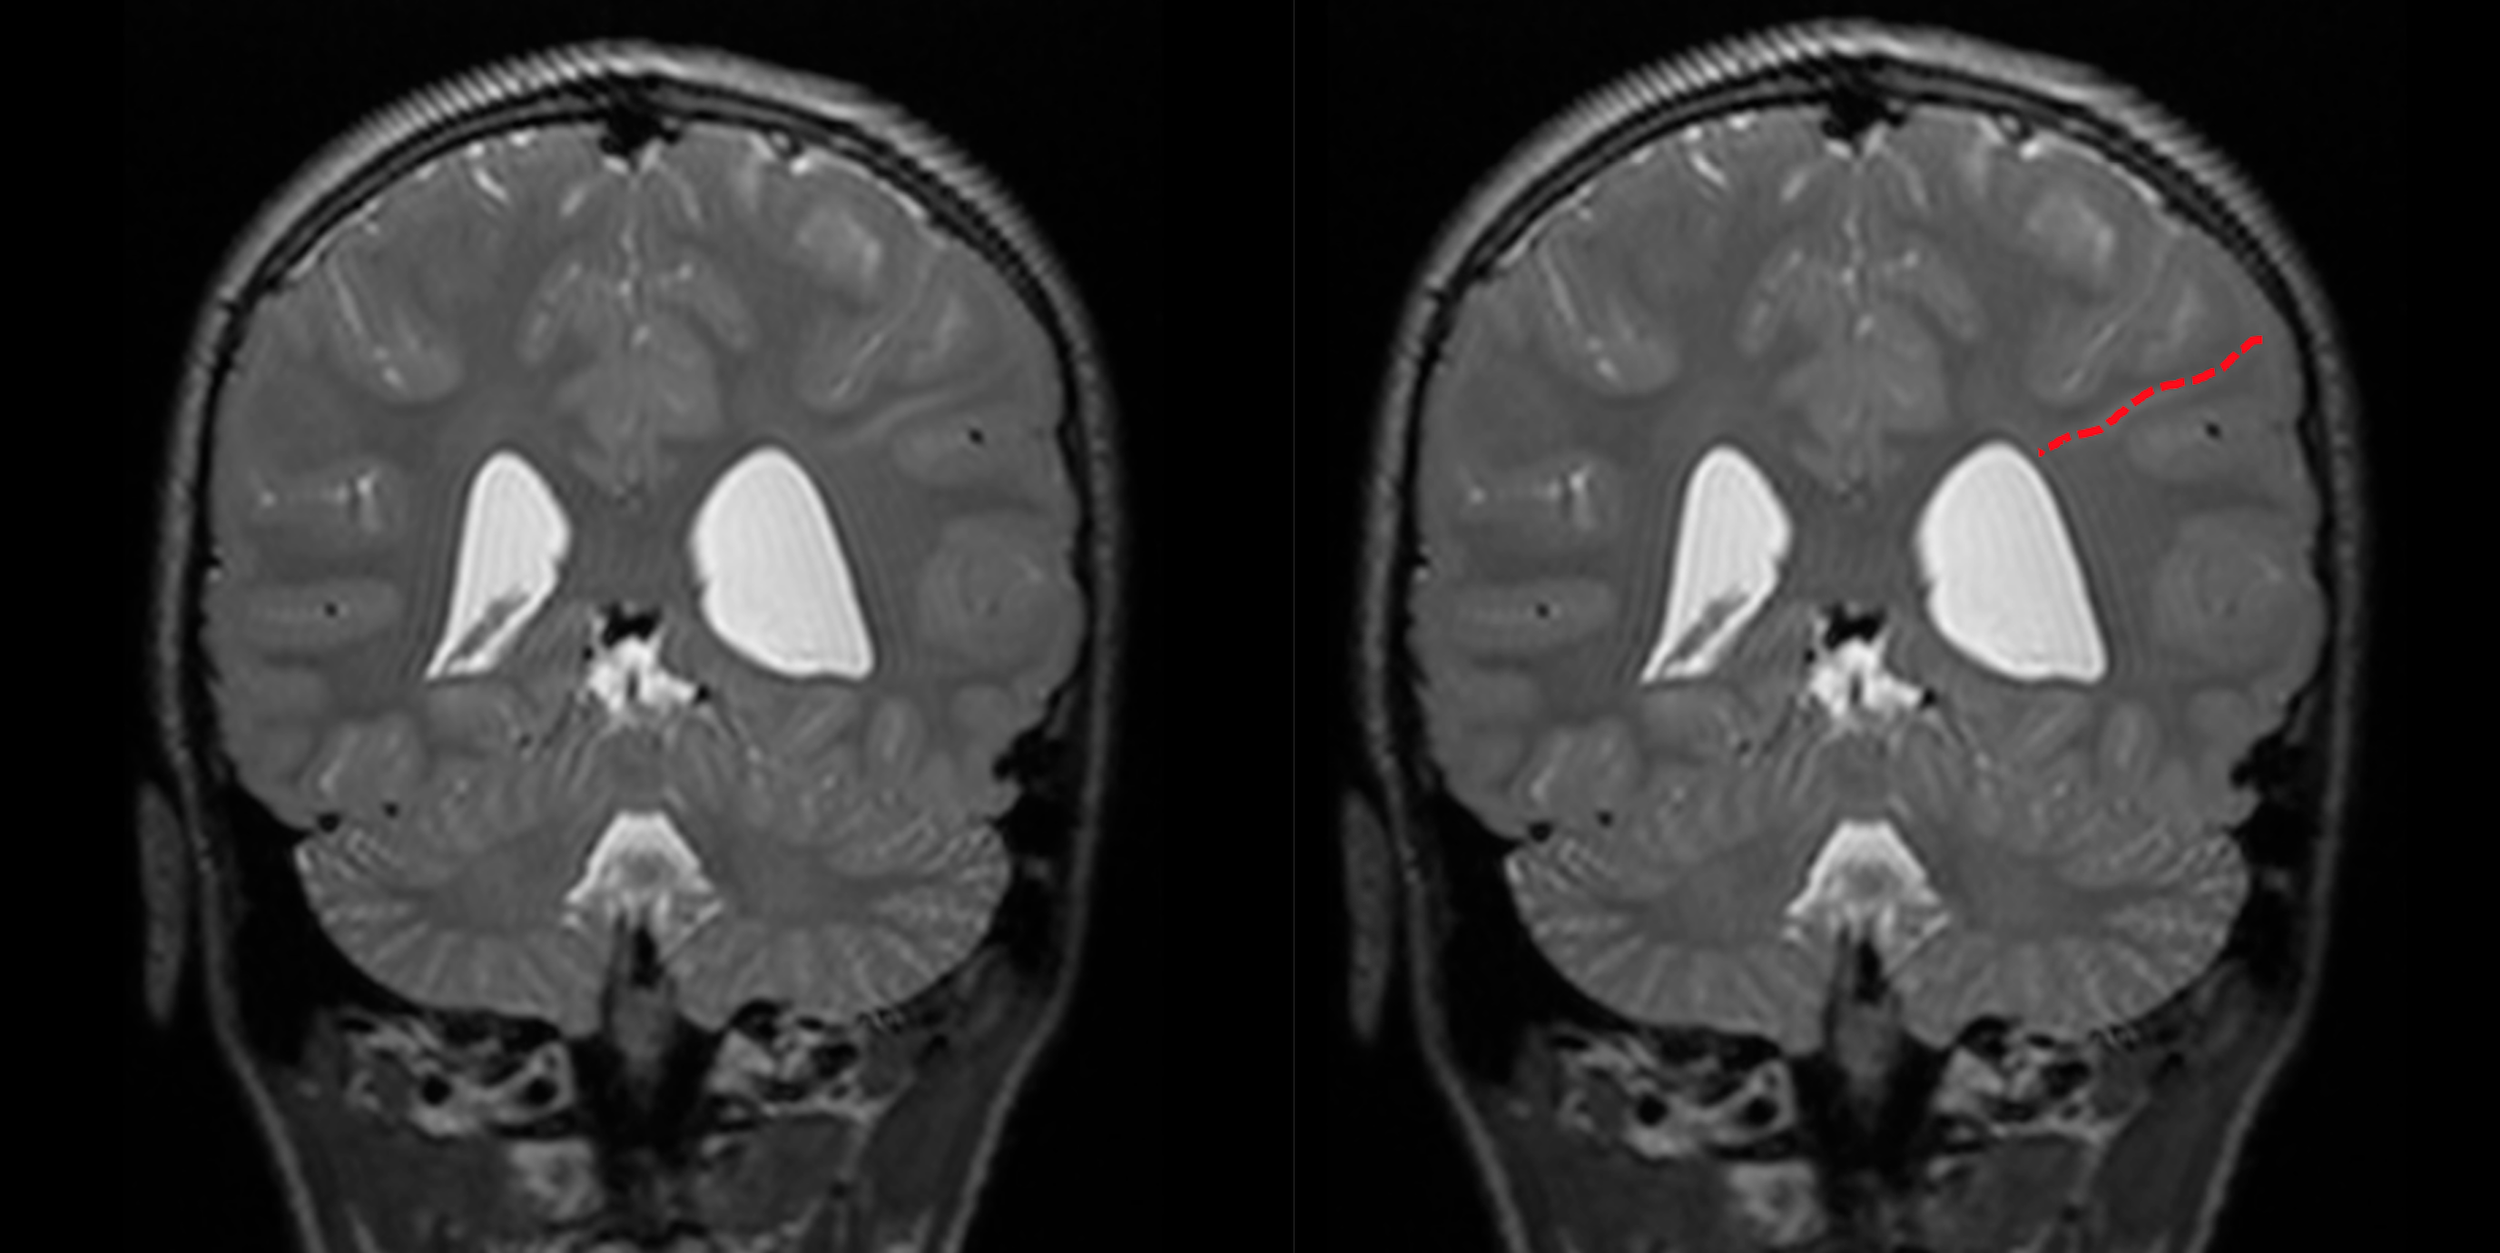

Radial Bands sign

• Linear bands radiating from periventricular white matter to the subcortical region

• MRI finding specific for Tuberous Sclerosis